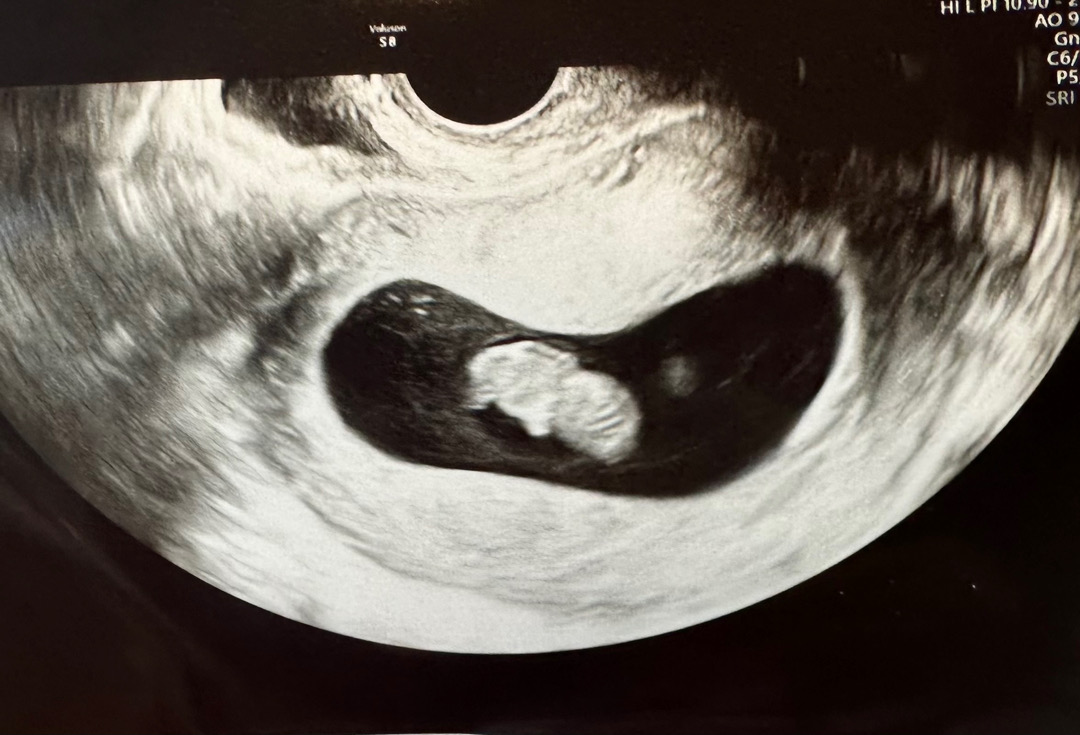

9주 1일차

출혈때문에 걱정이었는데 무사히 9주 넘겨 구미베어 보고왔어요 잘커줘서 너무 기특해요😚